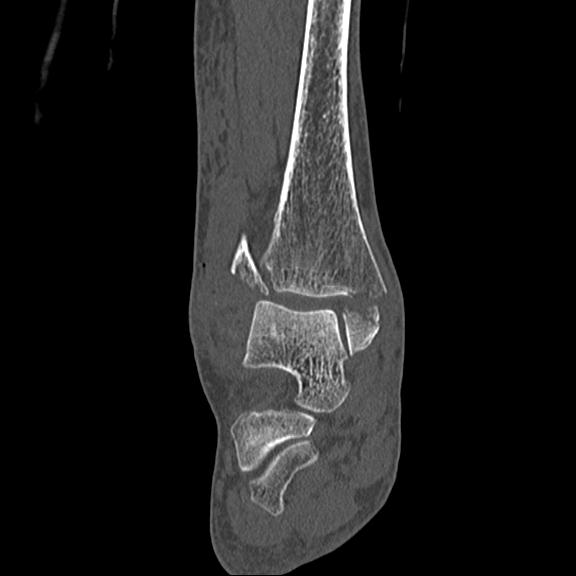

102755 1/4 2R 1/15 2R 右足関節 68歳女性 右三果脱臼骨折

56476 8/28 4R 1/21 2R 左足関節 デジカメ写真 72歳女性 右足関節AS